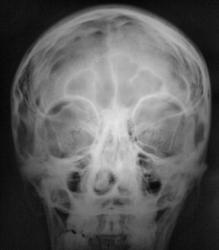

Пациент в ургентном порядке, после ДТП был доставлен в ЦРБ в ночное время. Был вызван "ургентный лаборант" для рентгенографии черепа. Пациент без сознания. С учетом состояния пациента рентгенография произведена в нестандартных проекциях - "задняя прямая".

А что скажите по поводу пирамидки и орбиты справа?

Контуры пирамиды чёткие, а вот латеральная стенка орбиты возможно сломана. Он был отправлен в ОКБ?

Линейный перелом с переходом на основание - дно средней черепной ямки. Сейчас вопрос о пирамидке и орбите не принципиальный. Главный вопрос нет ли внутричерпной гематомы. Если больной выйдет из тяжелого состояние, и встанут экспертные вопросы можно сделать Стенверс при потере слуха, Майер при кровотечении из уха. Насчет стенки орбиты - наличие перелома сомнительно, явно не видно. Также можно доснять при улучшении состояния. Судя по всему это молодой человек. Сколько лет?